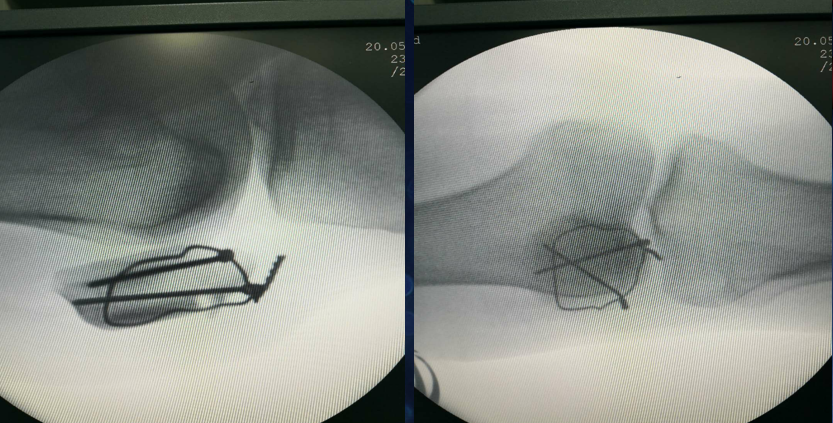

术中照

病房照

术后复查